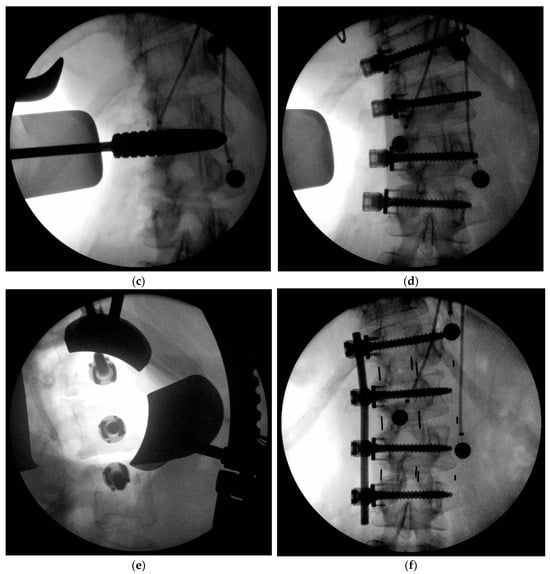

Figure 3.

Intraoperative images of the less invasive technique to the concave apex of the curve (a), The arrows indicate the planned trajectories and location for the wound incision. A radiographic marker is placed to confirm levels (b). Coronally tapered trials are used to determine interbody implant sizes starting at the end vertebral levels and working subsequently to the apical levels (c). The screw staple implants are then placed at the end vertebra first and then subsequently placed through the apical vertebral levels (d,e). Distraction is then applied between each segment and the rod secured to the transverse vertebral body screws (f).

After the endplates have been prepared and the transverse screws and staples have been placed, the coronally tapered interbody cages with or without lordosis combined with bone graft are placed working from the end intervertebral levels toward the apex. At this point, flexing the table and placing the coronally tapered implants achieves approximately 2/3 of the desired scoliosis correction as well as achieving lordosis. Spinal rotation usually spontaneously corrects due to the ligamentotaxis of the PLL and the release of the concave annulus. The appropriate length rod may be contoured in a slight lordosis if necessary and then placed into the screw heads. Manual retractors are preferred during this part of the procedure in order to expeditiously instrument the rod to the screws over multiple levels. Distraction is then applied between each segment and the rod provisionally secured with set screws to the transverse vertebral body screws (Figure 3f). This distraction maneuver, which may be repeated, accounts for an additional 1/3 of scoliosis correction. A final tightening of the set screws completes the instrumentation portion of the procedure.